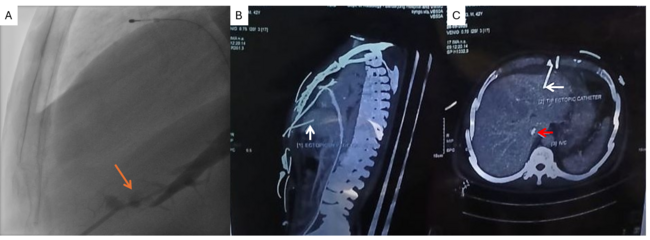

As lead-induced RV perforation causing tamponade was suspected, echocardiography-guided bedside pericardiocentesis was attempted via a 6F sheath. However, there was no hemodynamic improvement despite aspiration and autotransfusion. Contrast injection into the sheath showed opacification of a hepatic vein with trauma to the small branches (Figure A; Video). Another sheath was inserted under fluoroscopic guidance, through which 200 mL of hemorrhagic fluid was aspirated via pigtail (after confirming position with contrast) with hemodynamic improvement. The cardiothoracic surgery team advised computed tomography of the chest and abdomen, which showed the ectopic sheath lying in the hepatic parenchyma (Figure B and C). We switched to single antiplatelet with repeated pigtail drainage and output reducing over next 2 days. Under surgical backup, the ectopic sheath was removed with hourly abdominal girth and lactate monitoring. Subsequently, the temporary pacemaker lead was removed after 72 hours; the pigtail was removed 48 hours later. The patient was stable at discharge with no fluid re-accumulation.